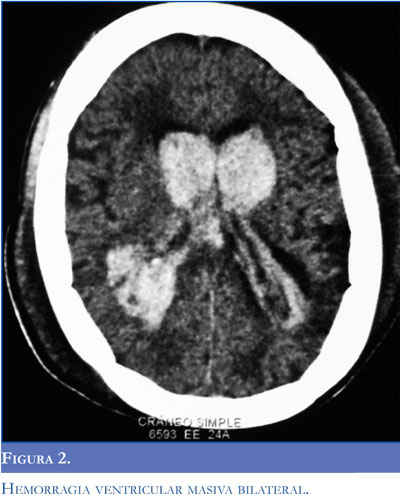

La paciente fue trasladada a la unidad de cuidados intensivos. No recuperó su estado de conciencia a pesar de suspender anestésicos y sedantes. Se realizó una tomografía de cerebro, que mostró hemorragia intraventricular masiva (Figura 2). Se consideró como diagnostico hemorragia intraventricular y estado convulsivo secundarios a hipertensión inducida por el embarazo con probable síndrome de HELLP.